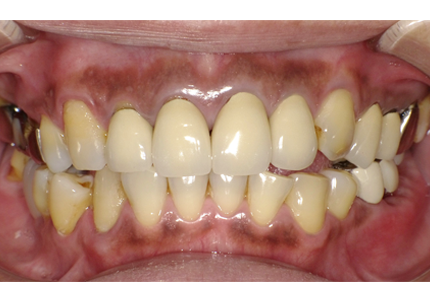

患者:Y.S 様

初診日 :2018年10月

主訴 :上顎前歯部審美障害、臼歯部補綴治療

1.初診時口腔内写真(2018年10月)